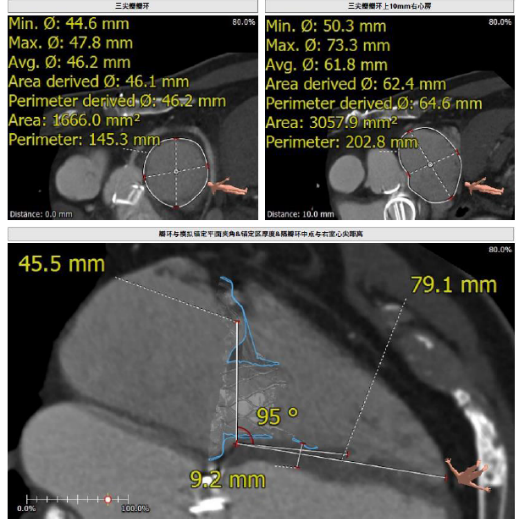

接受本次治療的是一例三尖瓣重度反流的患者,NYHA心功能Ⅲ級。主訴“反復活動后氣促1年,下肢水腫4個月”。入院N末端B型腦鈉肽前體(NT-proBNP)3161pg/ml。心電圖提示:心房顫動,ST-T改變。術(shù)前超聲提示:重度三尖瓣關(guān)閉不全,右心房擴大,三尖瓣收縮期位移(TAPSE)14mm,左房增大,左室收縮功能正常低值,主動脈瓣、二尖瓣機械瓣功能良好。術(shù)前CT評估(圖1):三尖瓣瓣環(huán)(周長換算直徑)大小為46.2mm;入路血管無嚴重迂曲,無鈣化;雙側(cè)冠脈有鈣化。